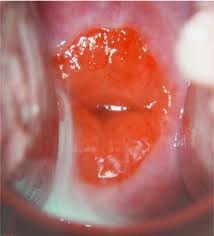

Imagine: Ectropion. Observati partea rosiatica care inconjuara orificiul colului uterin.

Exista cazuri in care colul uterin al adolescentelor, femeilor gravide sau al femeilor care folosesc anticonceptionale orale, sufera o transformare normala (datorata modificarilor hormonale) care se numeste ectropion. Acesta este caracterizat de aparitia in exteriorul colului uterin a stratului care in mod normal captuseste canalul colului uterin si care in alte conditii decat cele enumerate mai sus nu este vizibil.

Ectropionul reprezinta o varianta normala a colului si nu trebuie tratat decat in situatia rara cand femeia acuza secretii mucoase abundente sau sangerare vaginala dupa contactul sexual. Singurul lucru care trebuie facut in prezenta unui ectropion este un test Papanicolau (daca un astfel de test nu a fost facut in ultimile 12 luni) .